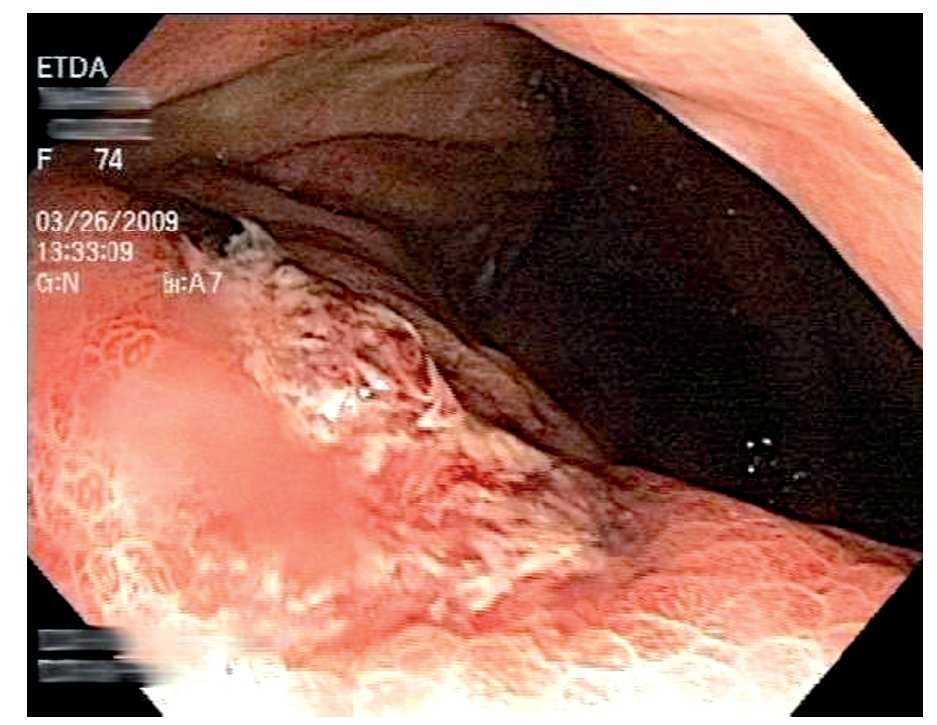

Mujer de 74 años de edad, residente del Distrito Federal, con antecedente de esclerodermia y cirrosis biliar primaria en tratamiento con ácido ursodeoxicólico. Inició ocho días previos a su ingreso con dolor abdominal epigástrico, náusea, distensión abdominal y melena. A la exploración física se encontró con signos vitales normales, mucosas pálidas, peristaltismo disminuido, sin otros hallazgos relevantes. Los exámenes de laboratorio mostraron hemoglobina 10.6 gr/dL, hematocrito 31%, leucocitos totales 8700 células/dL (4% de eosinófilos). Se le realizó endoscopia de tubo digestivo, que evidenció esofagitis erosiva grave, gastropatía eritematosa petequial, múltiples úlceras gástricas de 10 mm de diámetro con base de fibrina (Figura 1) y duodenitis erosiva (Figura 2). Se tomaron biopsias de los bordes de las ulceras y se envió en formol a estudio histopatológico que informó estrongiloidiasis gástrica, con inflamación crónica y aguda sin Helicobacter pylori (Figuras 3 y 4).

¿ Figura 2. Duodenitis erosiva.